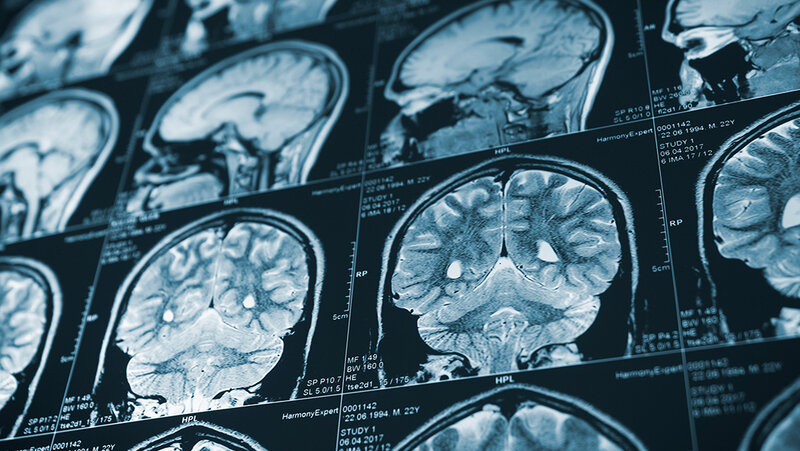

Wenn die Patientinnen und Patienten nicht kommunizieren können oder der Schlaganfall während des Schlafs stattgefunden hat, ist das medizinische Personal gefragt. In Form von CT-Bildern wurde bisher ermittelt, wann der Schlaganfall passiert ist. Je dunkler die betroffene Region im CT auftritt, desto länger liegt der Schlaganfall zurück. Doch auch der individuelle Blutfluss und die Blutgefäßstruktur beeinflussen, wie schnell der Schaden voranschreitet.

Hier greift nun ein Algorithmus ein. Forschende der Technischen Universität München, in Zusammenarbeit mit dem Imperial College London, lernten einen Algorithmus mit 800 CT-Bildern von Schlaganfallpatientinnen und -patienten an. Mit dieser Grundlage identifiziert die KI die betroffene Hirnregion und gibt einen Zeitpunkt des Schlaganfalls an.